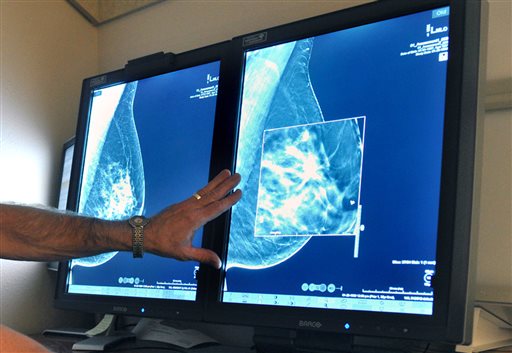

CHICAGO (AP) — The American Cancer Society now says women should start mammograms later in life and get fewer of them, a stance that puts the trusted group closer to an influential government task force’s advice.

In new guidelines out Tuesday, October 20, the cancer society recommends that most women should begin annual screening for breast cancer at age 45 instead of 40, and switch to every other year at 55. The task force advises screening every other year starting at age 50.